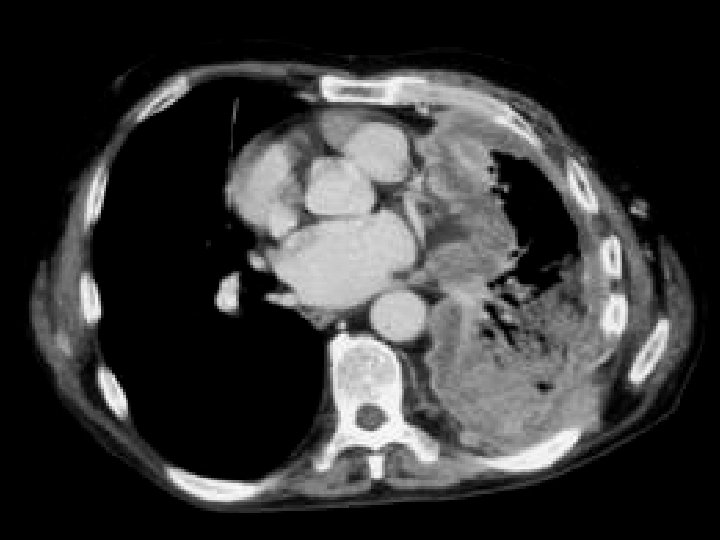

Pancreatic pseudocysts • Findings: – Multiple large pancreatic cystic lesions • ddx: – Von-Hippel Lindau – Cystic pancreatic neoplasm